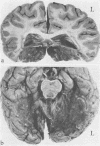

Two long-surviving cases of cortical blindness are described, one total and the other total except for detection of sudden transitions from light to darkness and darkness to light. Both suffered from severe defect of recent memory, which lasted a month in one, and till death after nearly six years in the other. One patient survives. Necropsy findings on the other are given.

Images in this article